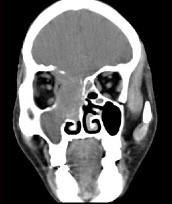

问题 女性,53岁,右侧鼻腔流血近1年,近来头痛,行CT检查如图所示,请选择正确的答案()

选项 A.鼻腔癌 B.鼻腔内息肉 C.副鼻窦炎 D.鼻腔炎性假瘤 E.鼻腔内血管瘤

答案 A